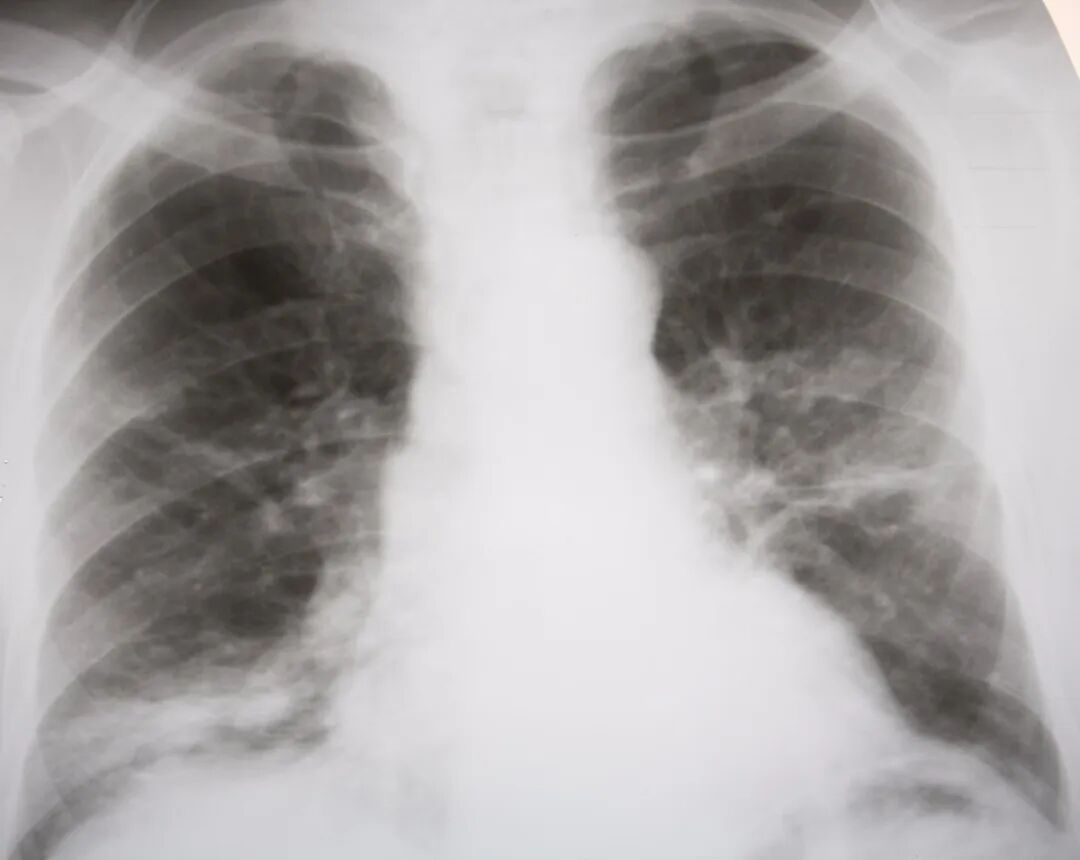

肺心病,全名叫慢性肺源性心脏病或慢性肺心病,是由肺组织、肺血管或胸廓的慢性病变引起肺组织结构或功能异常,产生肺血管阻力增加,肺动脉压力升高,使右心室扩张或肥厚,伴或不伴右心功能衰竭的一类心脏病。

肺心病是慢性阻塞性肺病,常反复发作。在我国是常见病、多发病,具有高流行性、高患病率、高死亡率和高费用的四高特点,是成人患病和死亡的重要原因之一。